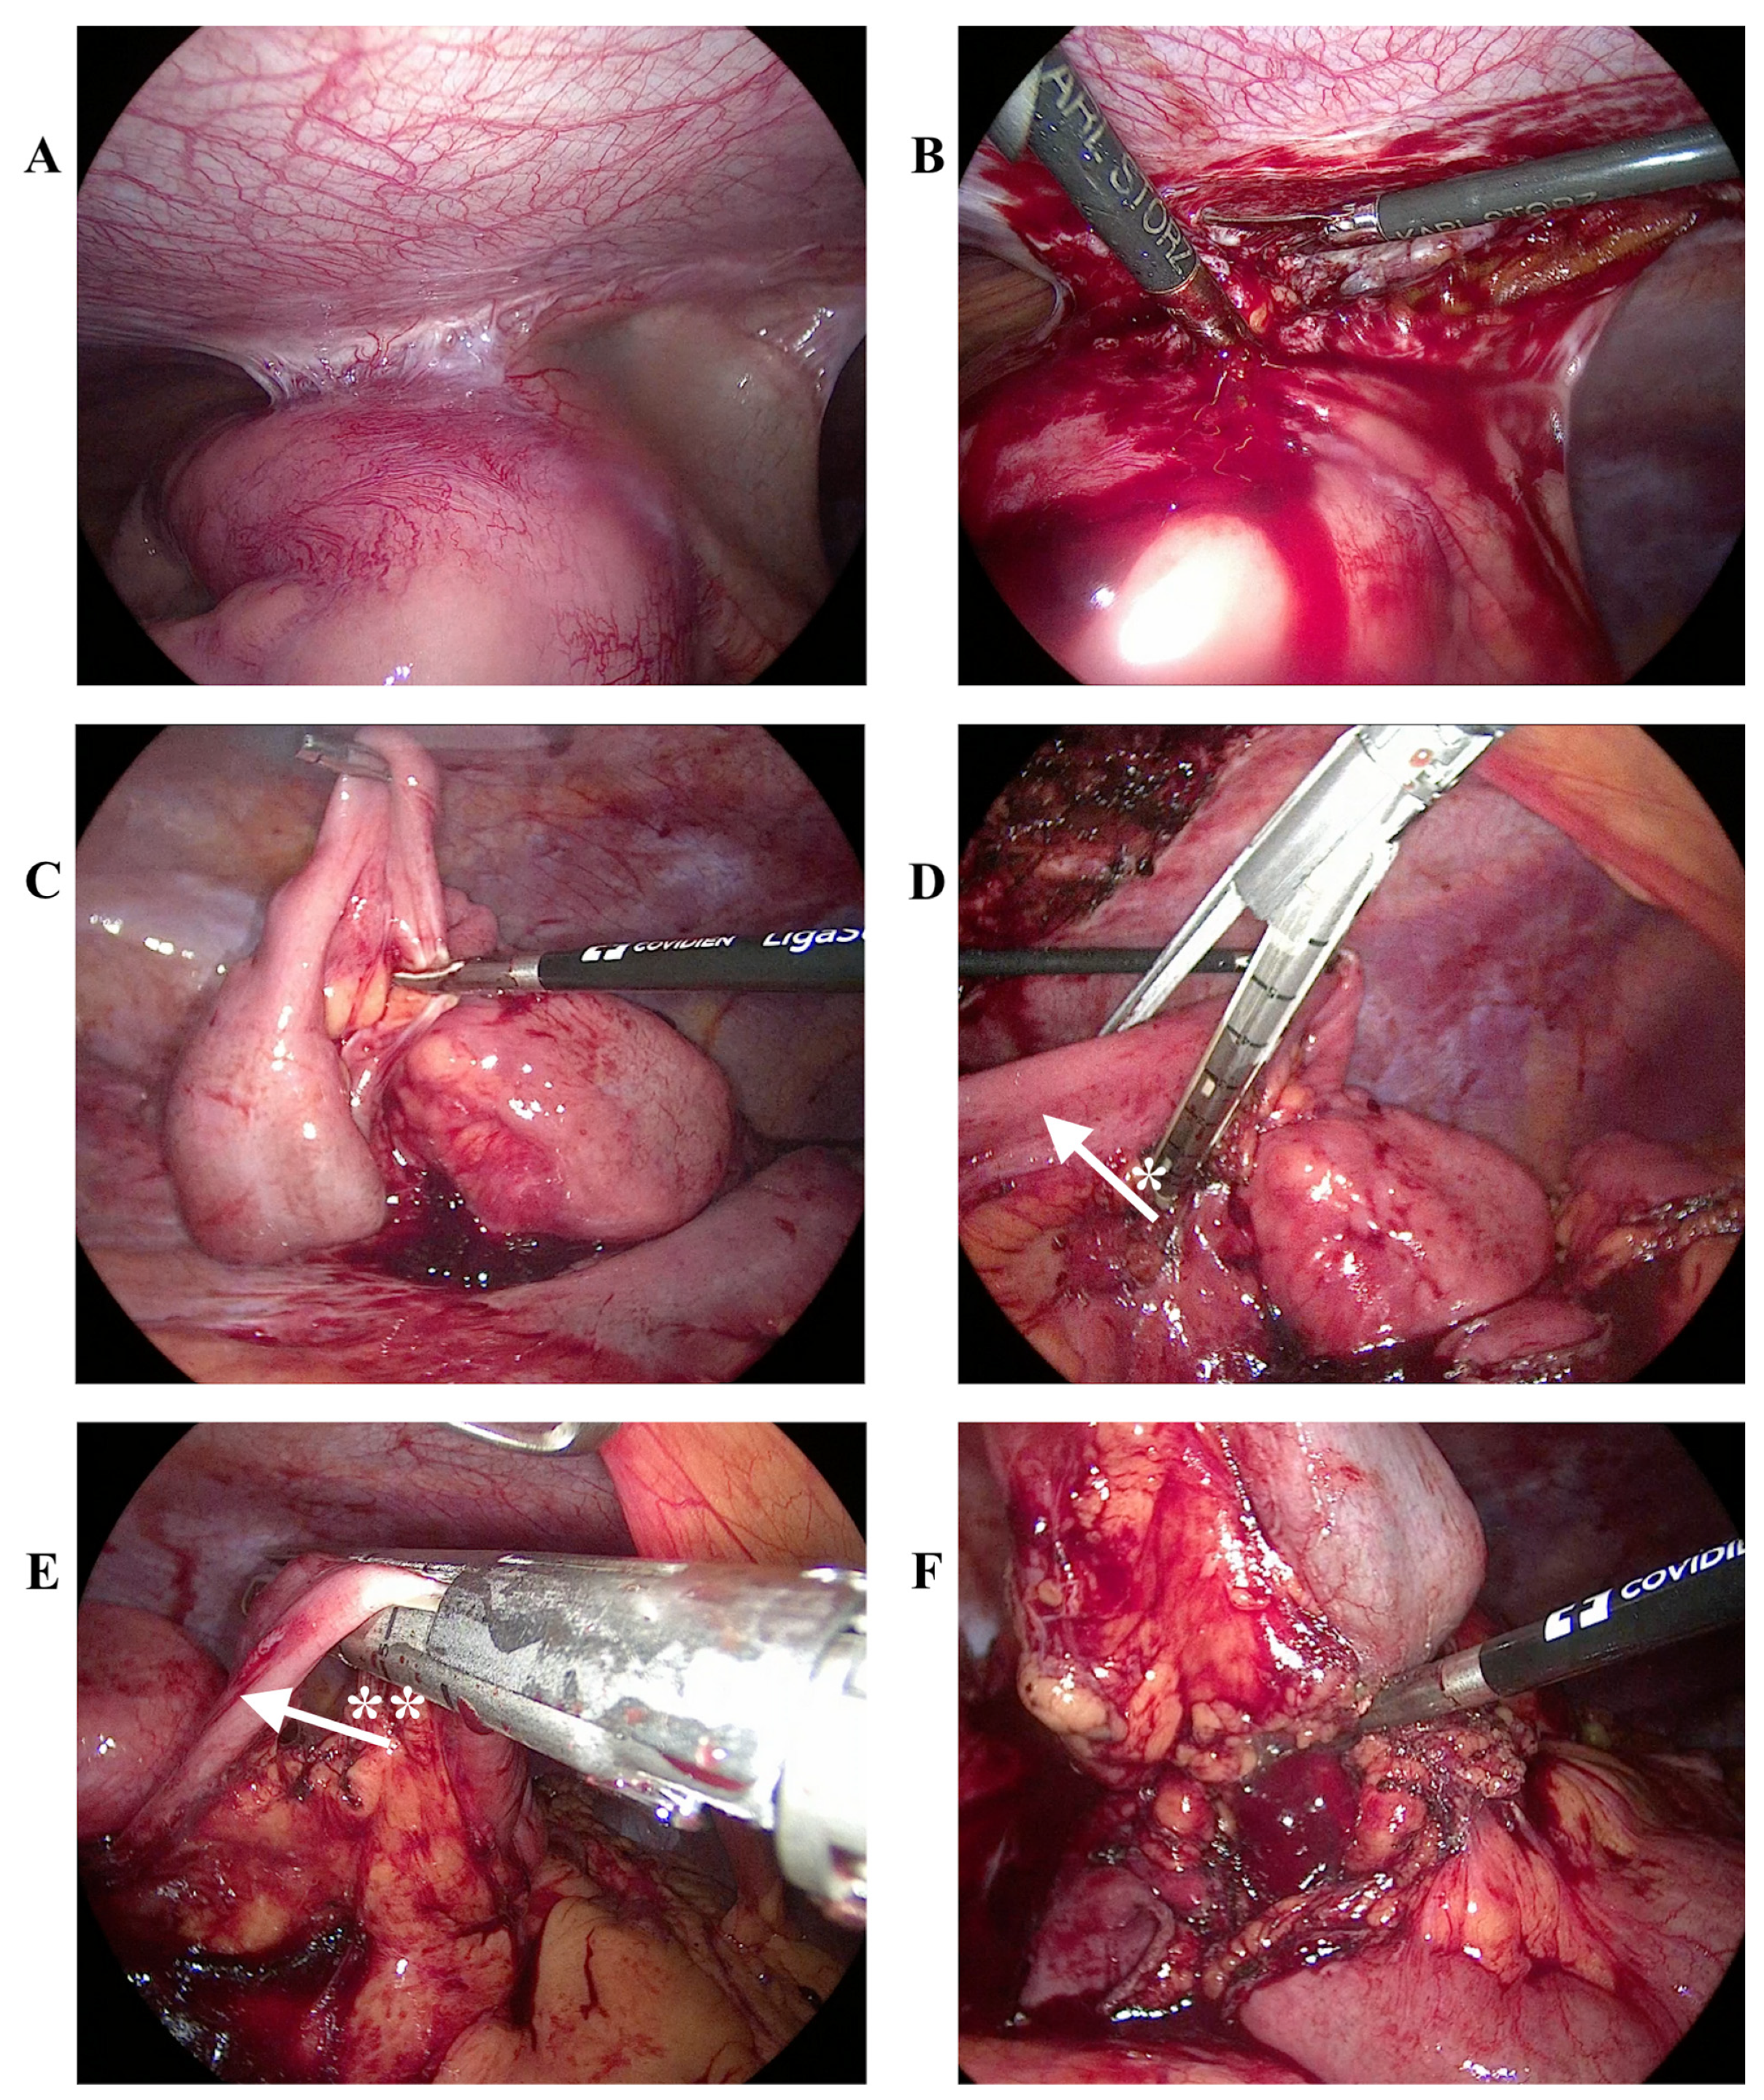

Successful Laparoscopy-Assisted Extirpation of Burkitt’s Lymphoma Causing Intestinal Obstruction in a 17-Year-Old Boy

2. Case Report